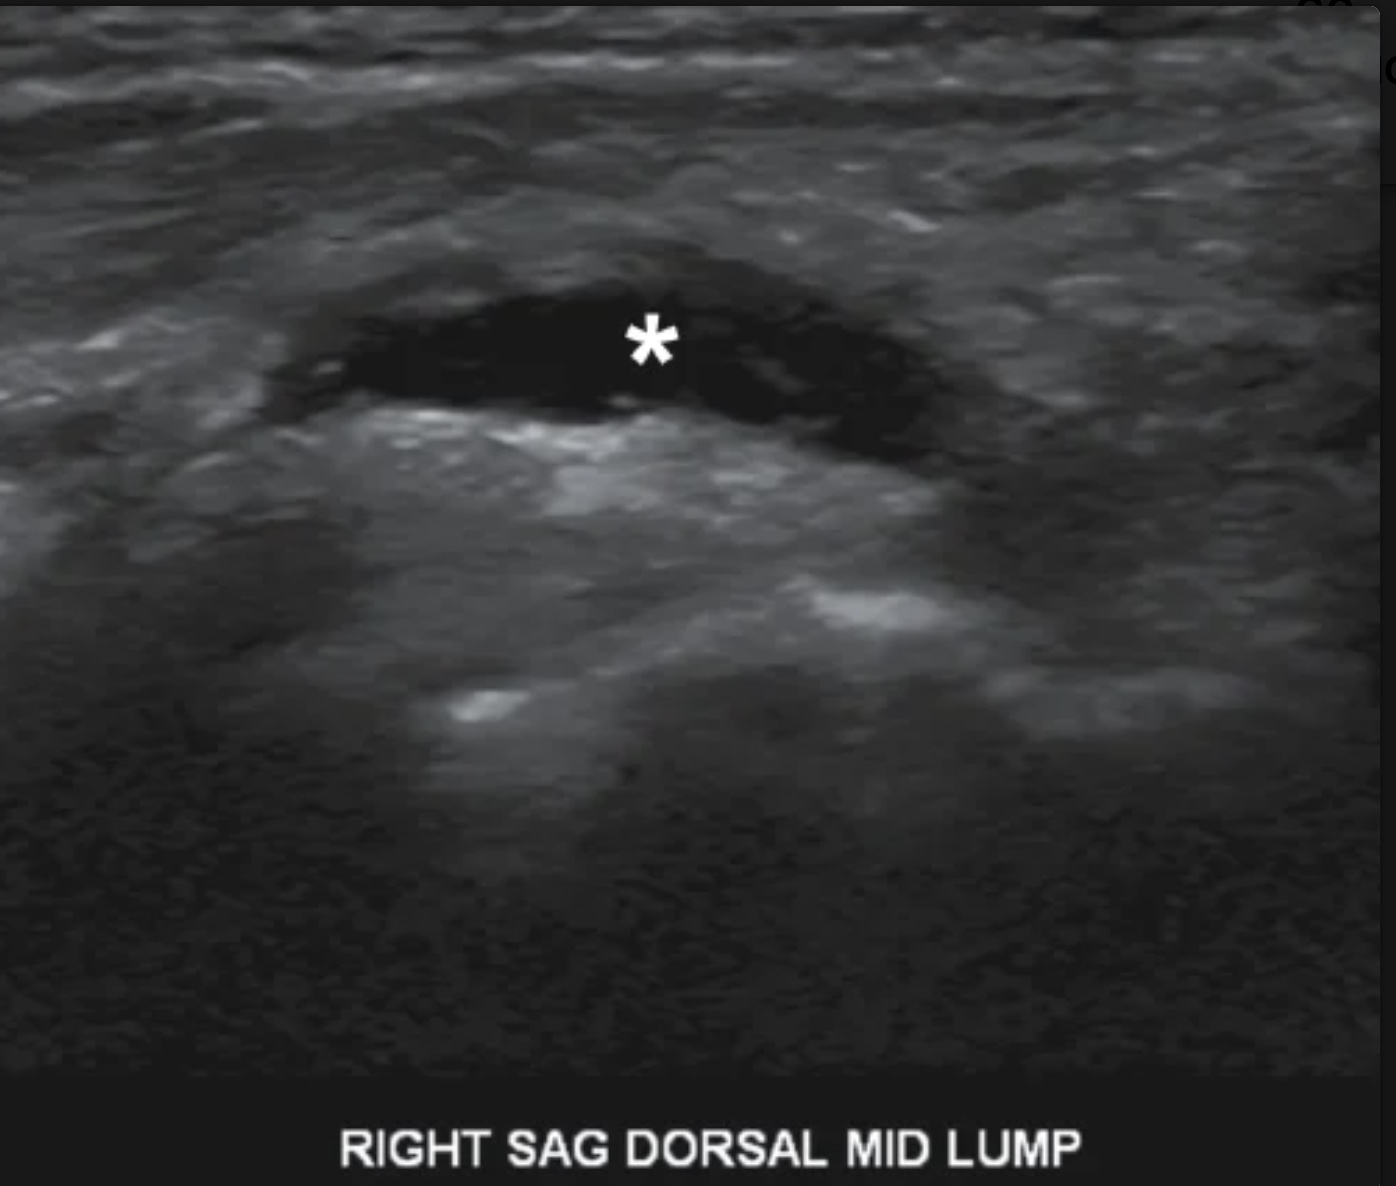

The masses in image were discovered in lactating patient who were suffering from focal breast erythema, swelling, fever, & rain. What is the most likely diagnosis

breast abscess

What lab would most likely be elevated in the patient with this image

White blood cell count